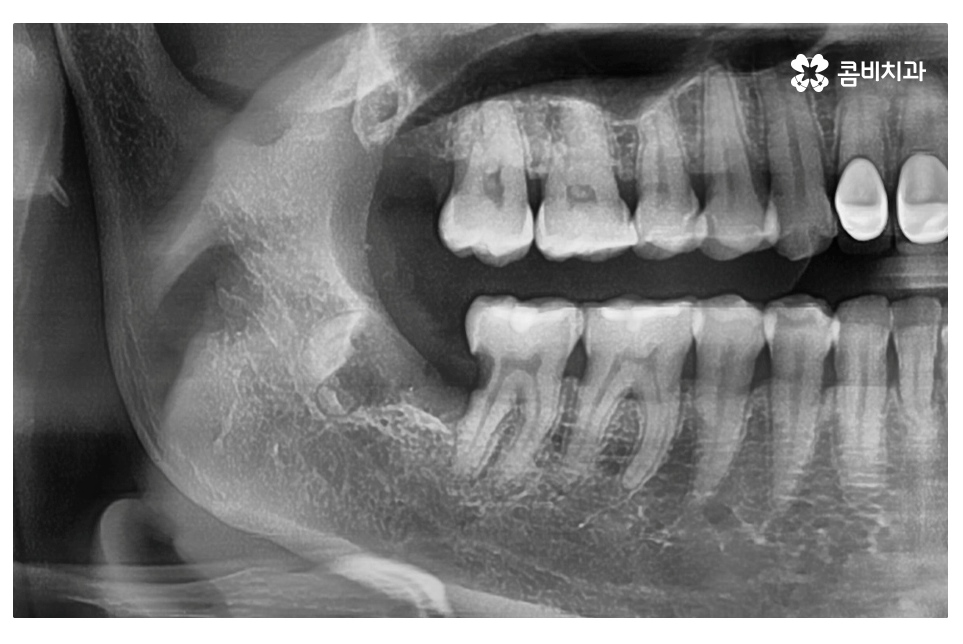

한국인들의 경우 사랑니가 매복되어 있는 경우가 많으며

어금니에 충치를 유발하는 경우 외에도

잇몸에 염증을 일으키면서 그로 인해 턱뼈 손상을 유발하는 경우도 있는데요.

매복된 사랑니가 누워서 자라는 경우에는 눈으로는 상태를

확인할 수 없기 때문에 통증이나 불편한 증상을 느끼고

치과를 찾는 경우에 이미 치료가 늦는 경우가 많으며

이번 케이스처럼 멀쩡한 어금니까지 손상이 발생하는 경우도 있어요.